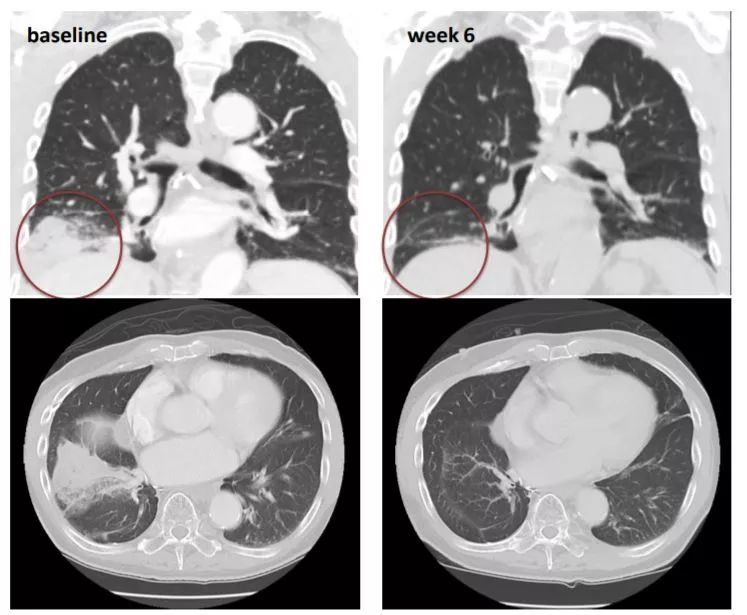

非小细胞肺癌靶向NRG1-CD74治疗前及治疗6周后CT影像:患者咳嗽消失,肿瘤缩小